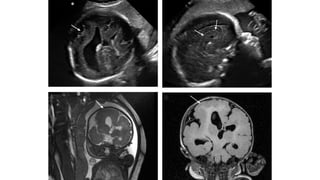

TRANSTORNOS DE PROLIFERACIÓN: MICROCEFALIA

• Antenatally is even more difficult, because affected fetuses have usually

normal cranial measurements in early gestation, that only decline in late

gestation or after birth.

• The incidence is estimated to be 1.6 per 1000 singlebirth deliveries. Only

14 % of all microcephalic infants diagnosed by the first year of age had

been detected at birth.

• The available literature suggests that the risk of mental retardation with an

head circumference between – 2 and – 3 SDs is in the range of 10-30%,

rising to 50-60% for measurements below – 3 SDs.

G.MALINGER G.MALINGER

G.PILU

Daniel-Spiegel et al—Establishment of Fetal Biometric

Charts Using Quantile Regression Analysis. J Ultrasound

Med 2013; 32:23–33 | 0278-4297

24ss